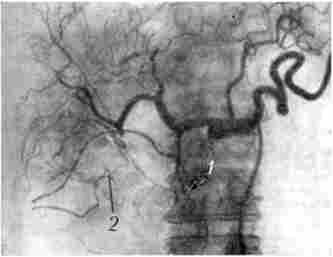

Для виявлення зв'язку пухлини з судинами і уточнення ангіоархітек- топіки застосовується ангіографія. При раку підшлункової залози виникають зміни в її судинах або судинах, розташованих в безпосередній близькості: змінюється просвіт і положення судин, порушується кровообіг, з'являються атипові судини. Існує кілька методик контрастування артерій і вен ПЖ:

Для пухлини характерні зміщення, деформація, оклюзія судин (рис. 21.12). Діагностична точність методу складає близько 70%.

Целіакограмма. Рак головки підшлункової залози

Мал. 21.12. Целіакограмма. Рак головки підшлункової залози,

артеріальна фаза: